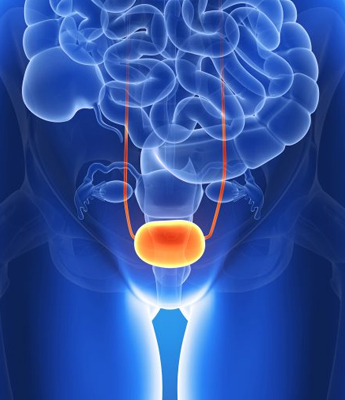

The prostate gland is a small, walnut-sized exocrine gland located at the base of the bladder. It plays a vital role in the male reproductive system by producing a significant portion of semen and providing nourishment to sperm, essential for their transport and protection during ejaculation. Disorders of the prostate, which are common in men over the age of 45, can significantly impact prostate function and overall health. Conditions such as Benign Prostatic Hyperplasia (BPH) cause the prostate to enlarge and may lead to urinary difficulties, while Prostatitis, an inflammation often resulting from infections or other causes, can produce symptoms like pelvic pain and urinary discomfort.